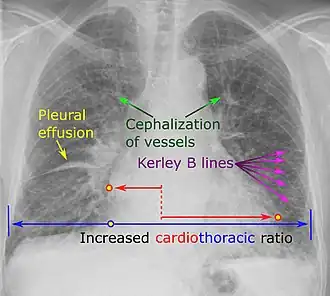

Chest X-ray

Chest X-rays are frequently used to aid in the diagnosis of CHF. In a person who is compensated, this may show cardiomegaly (visible enlargement of the heart), quantified as the cardiothoracic ratio (proportion of the heart size to the chest). In left ventricular failure, evidence may exist of vascular redistribution (upper lobe blood diversion or cephalization), Kerley lines, cuffing of the areas around the bronchi, and interstitial edema. Ultrasound of the lung may also detect Kerley lines.[73]

Kerley B lines

Kerley B lines